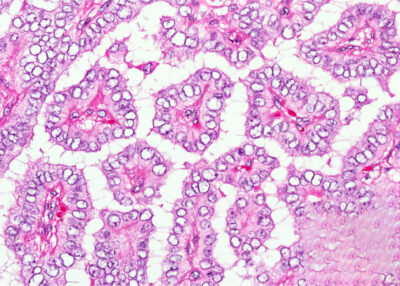

Bu gruptaki hastalar daha çok 40-60 yaş arası kadınlardır. Tiroid kanserlerinin %5 ini oluştururlar. Folliküler kanserler tiroid kanserleri içinde tanısı en zor konan gruptur. Zira bu grupta gerek ameliyat öncesi yapılmış olan ince iğne biyopsisinde gerek ameliyat sırasında yapılan dondurarak hızlı inceleme (frozen section) de lezyonun bir kanser olup olmadığını anlamak mümkün değildir. Zira bu türde kanser olup olmadığı ancak normal yapıdaki hücrelerden oluşan bu kitleyi çevreleyen kapsülün herhangi bir yerinde hücrelerin bu kapsülü delip dışarı çıkıp çıkmadığının görülmesi ile konabilir. Kapsülün bu şekilde bir istilası durumunda folliküler kanser, kapsülün sağlam kalması halinde iyi huylu folliküler adenom tanısı konur.

Tedavileri papiller tipte olduğu gibi total tiroidektomi ve istila yapmış kanser durumunda tümör büyüklüğü ne olursa olsun ameliyat sonrası radyoaktif iyot tedavisi şeklindedir. Hastaların % 80 i başarılı bir tedavi ardından normal sağlıklı yaşamlarını sürdürürler.